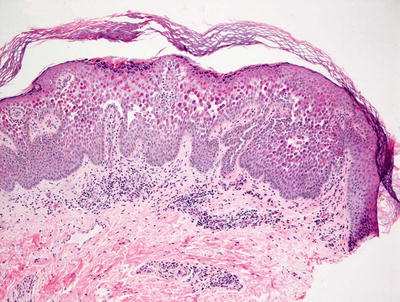

3.9.2 Histology

Histologic features of Hailey–Hailey disease show an epidermis with varying degrees of spongiosis and acantholysis. The stratum corneum has normal thickness. The roof of the intraepidermal blister is often fragmented with single keratinocytes separating from other keratinocytes, the so-called “dilapidated brick wall” appearance (Figs. 3.21 and 3.22). Dyskeratotic cells are not abundant. An inflammatory infiltrate that is predominantly lymphohistiocytic with scattered eosinophils is present and may extend into the epidermis [63, 64].

Fig. 3.21

Hailey–Hailey disease shows a mid-epidermal or suprabasilar blistering process within a spongiotic epidermis

Fig. 3.22

The roof of the blister in Hailey–Hailey disease appears to be disintegrating as individual keratinocytes separate into the blister cavity from above